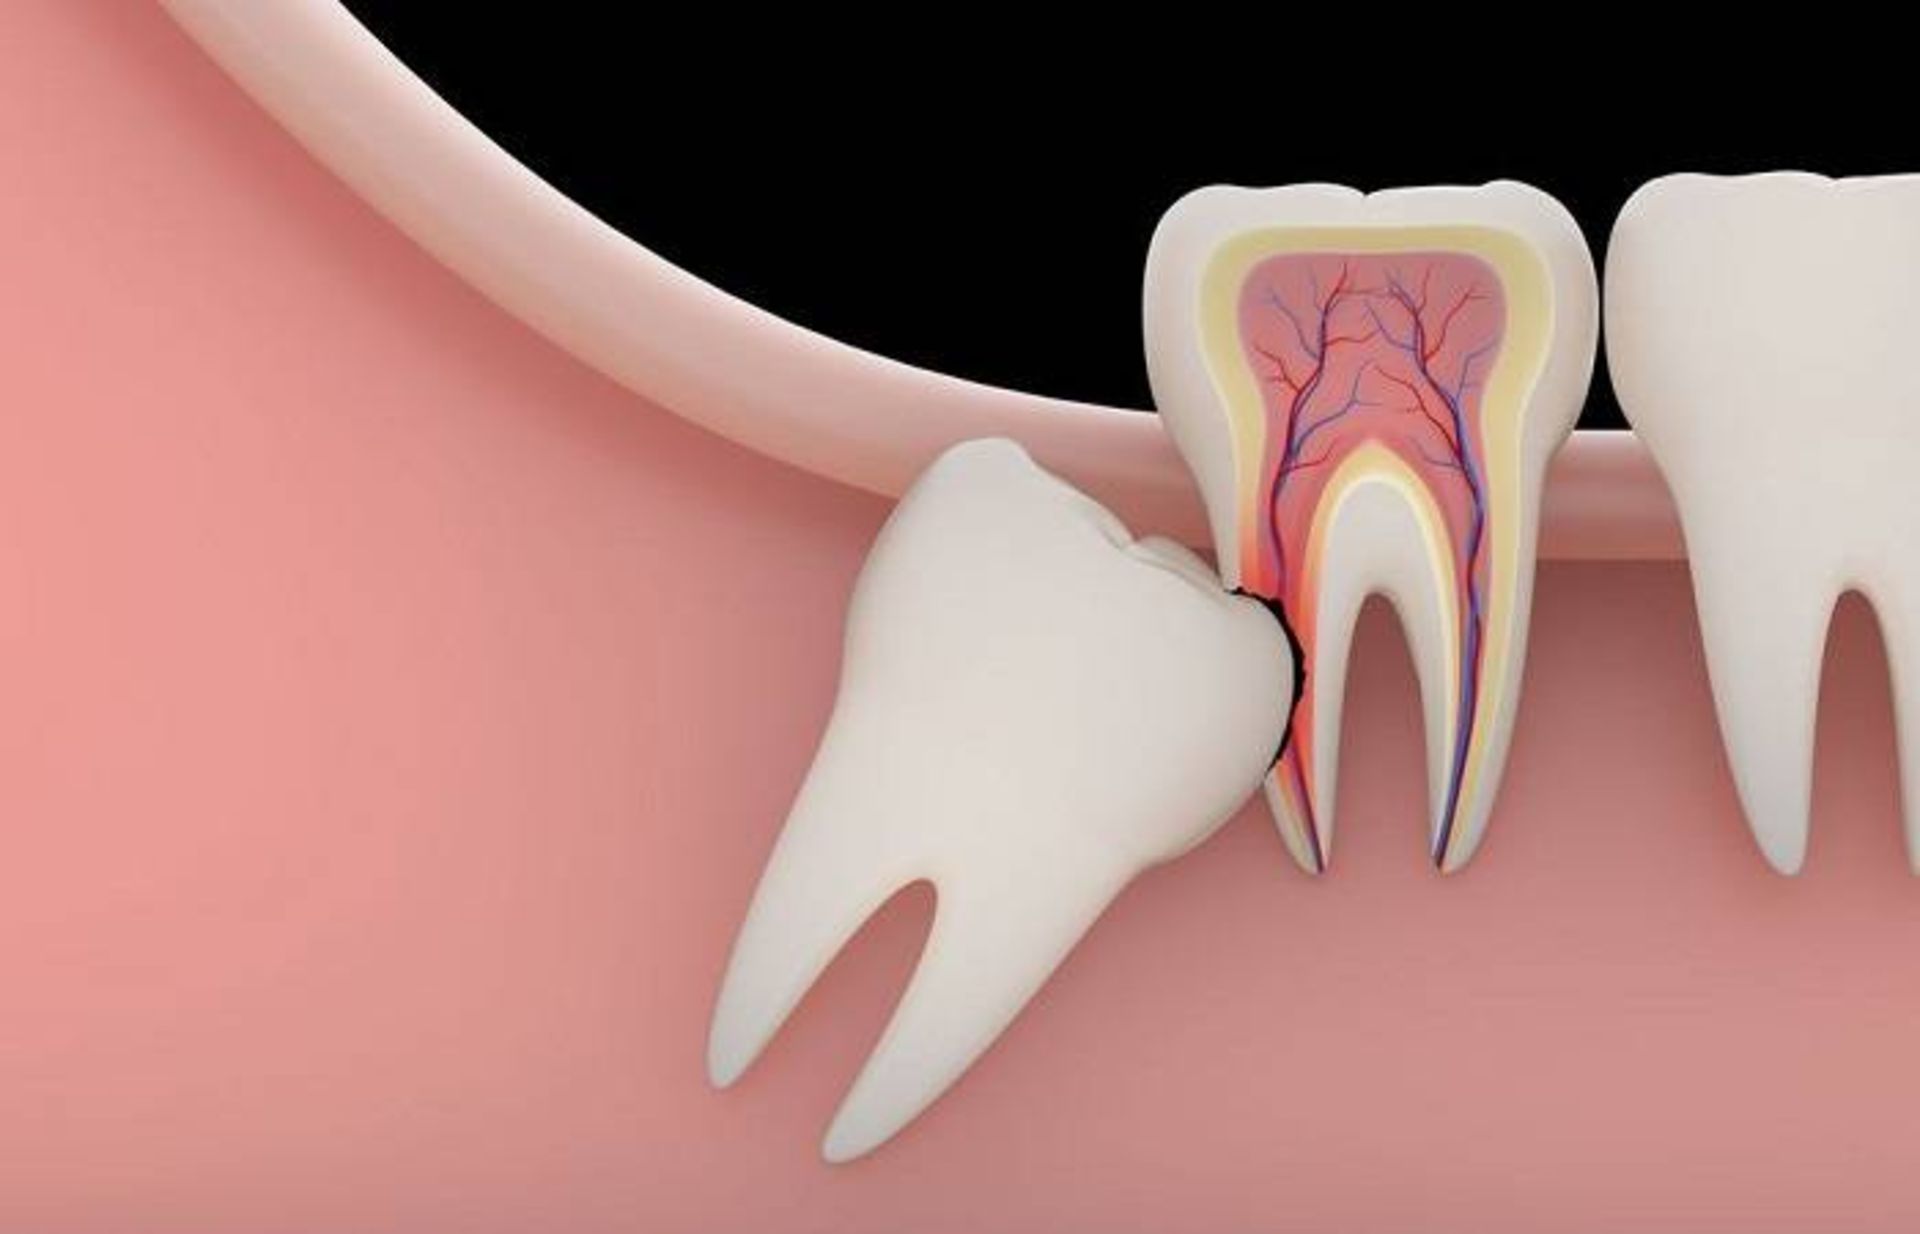

با‌این‌حال، فقط اینکه دردی از جانب دندان‌های عقل خود احساس نمی‌کنید، بدان معنا نیست که هیچ مشکلی وجود ندارد. این دندان‌ها ممکن است گیر افتاده یا نهفته باشند. این بدان معنا است که آن‌ها نمی‌توانند از فک خارج شوند و وارد دهان شوند. شاید دهان شما بسیار کوچک است و فضایی برای آن‌ها وجود ندارد یا این دندان‌ها به سمت دندان‌های دیگر در حال رشد باشند. آن‌ها می‌توانند به دندان مجاور فشار وارد کرده و به آن آسیب بزنند.

آسیب زدن به دندان‌های دیگر: این مجموعه اضافی از دندان‌های آسیاب بزرگ می‌تواند به دندان‌های دیگر فشار آورده و موجب درد دهان و مشکلات گاز گرفتن شوند (ایجاد مشکل در قرار گرفتن دندان‌ها روی هم).

آسیب فک: کیست‌هایی ممکن است اطراف دندان جدید تشکیل شوند. در صورت عدم درمان، این کیست‌ها می‌توانند فک را خالی کرده و به اعصاب آسیب بزنند.